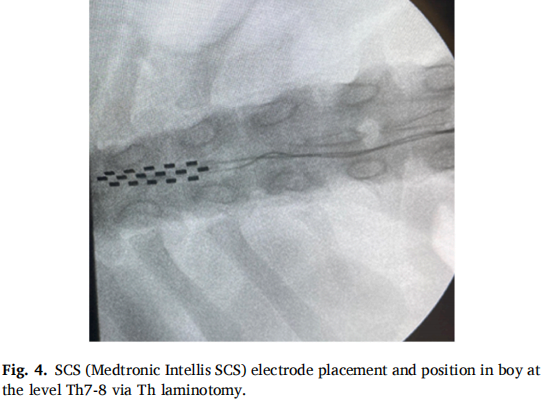

本研究采用 SCS硬膜外電極植入。病例1(CRPS1女性患者)接受下肢電極經(jīng)皮植入T10水平,上肢電極通過(guò)右側(cè)C6-C7椎間盤(pán)切除術(shù)放置;病例2(CIDP男性患者)通過(guò)T8椎板切開(kāi)術(shù)在T7-8水平植入電極。兩例均在全身麻醉下完成手術(shù),避免使用神經(jīng)肌肉阻滯劑以保留運(yùn)動(dòng)信號(hào)監(jiān)測(cè)能力。植入后設(shè)置10天試驗(yàn)期評(píng)估療效,確認(rèn)有效后植入永久脈沖發(fā)生器。術(shù)中采用透視引導(dǎo)確保精準(zhǔn)定位,術(shù)后定期調(diào)整刺激參數(shù)以?xún)?yōu)化治療效果。病例2因腦脊液泄漏經(jīng)歷三次電極位置調(diào)整,最終更換為椎板切開(kāi)術(shù)植入新電極。

圖片4.png

圖4